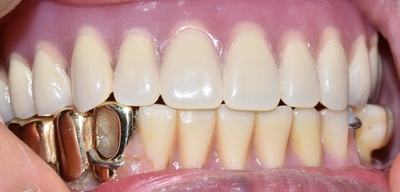

![[종로/시청역]실제 환자의 보험 임플란트, 보험 틀니 사례 소개합니다. 젊어지는틀니,임플란트 치료 관련 이미지 1](https://pub-9f2bb3498faf4d1d8714b41df24753e3.r2.dev/content/clinics/archive/rseeanjxfu/naver_blog/yonseiyegam/assets/by_hash/d1296b66afc44406b1f5ab339ff9eacc4f773c83630b6040a83e60c9839f33e5.jpg)

![[종로/시청역]실제 환자의 보험 임플란트, 보험 틀니 사례 소개합니다. 젊어지는틀니,임플란트 치료 관련 이미지 2](https://pub-9f2bb3498faf4d1d8714b41df24753e3.r2.dev/content/clinics/archive/rseeanjxfu/naver_blog/yonseiyegam/assets/by_hash/6bbe6c0f547e018d15387f5b63ec402c4b1f57ca65909b0869fed9c55d242483.png)

틀니를 빼면 위 사진과 같은 상태였고요

엑스레이에서 보듯이 이가 많이 없으셨죠.